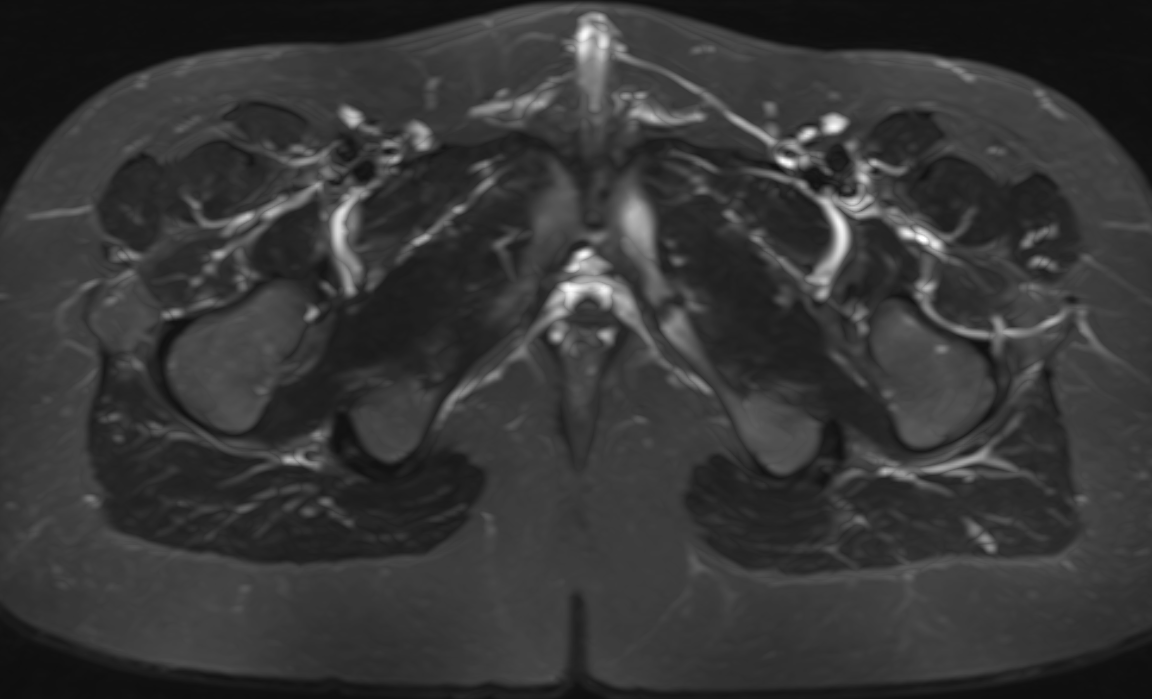

Van Neck Odelberg Disease - Ischiopubic Synchondritis